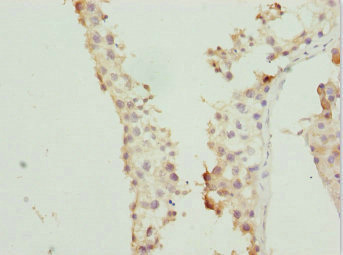

圖片:

應(yīng)用范圍:ELISA, IHC

Application Recommended Dilution IHC 1:20-1:200 -